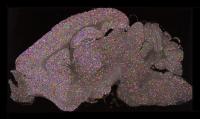

image: Young mouse brain section showing lower synapse diversity. Credit Zhen Qui and Seth Grant University of Edinburgh. view more

The colourful pictures of the whole mouse brain at different ages are the first of their kind and a pivotal step forward in understanding behaviour, scientists say.

The images are of synapses - vital connections that carry electrical and chemical messages between brain cells. Synapses store memories and synapse damage is linked to more than 130 brain diseases.

Researchers based at the University of Edinburgh colour-coded the different types of molecules to highlight the range of synapses in mouse brains from birth to old age.

Images from middle-aged brains burst with colour, illustrating a wide variety of synapses. Both very young and very old brain show less synapses and less complexity.